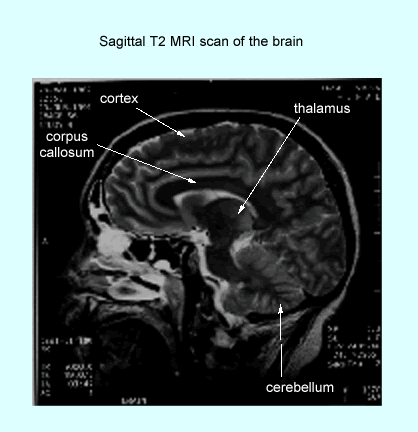

MRI brain scan (sagittal section)